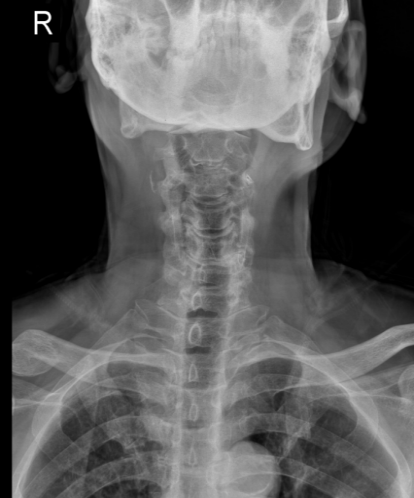

面对这一特殊情况,吴静晔主任没有急于下结论,而是为患者进行了细致全面的检查,最终精准诊断为脊髓型颈椎病。而进一步检查显示,患者存在 C3-T1 多节段狭窄,病情复杂且手术节段较多,这无疑给治疗带来了巨大挑战。

看似确定了治疗方向,真正的难题才刚刚开始。该手术区域解剖结构极其复杂,毗邻人体重要的神经、血管,堪称脊柱外科的「珠峰」。尤其是 C7-T2 椎弓根螺钉置入环节,传统手术极度依赖术中 C 臂透视,却因肩部遮挡,透视、定位极为困难,不仅手术视野受限、置钉难度陡增,螺钉还极易误入椎管,导致术中减压不充分,手术效果完全依赖主刀医生的丰富经验和精湛技术,是业内公认的「硬骨头」手术。